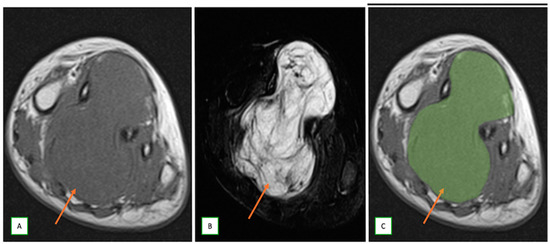

- Primary Sarcomas: Soft-tissue sarcomas are uncommon, accounting for just over 1% of adult malignancies. Synovial sarcoma, clear cell sarcoma, and epithelioid sarcomas are known to involve peripheral nerves. CT/MR reveals a large soft tissue mass with areas of necrosis or calcification and heterogeneous contrast enhancement. F-18 FDG uptake is useful for both tumor staging and treatment assessment (Figure 26, Figure 27 and Figure 28).